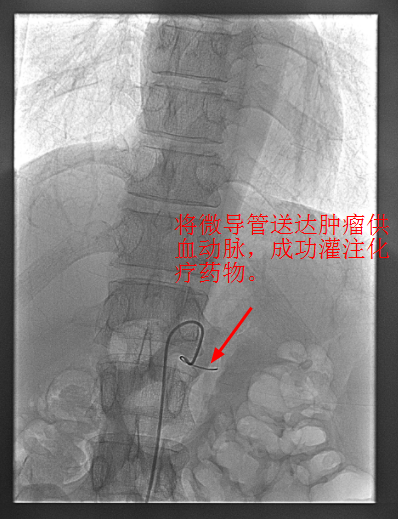

4月30日下午,李旭丹主任與胡志華主任上台實施介入化療術,在DSA造影下,清晰可見胰腺腫瘤的供血動脈,專家們将微導管經股動脈穿刺送達瘤體的供血動脈,成功将化療藥物灌注至瘤體,順利完成手術。術後,患者症狀明顯好轉,并于5月4日順利出院。